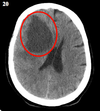

Qual a densidade do sangue fresco na TC?

hiperdenso

(imagem = TC de área hiperdensa com efeito de massa - hematoma frontal e recente)